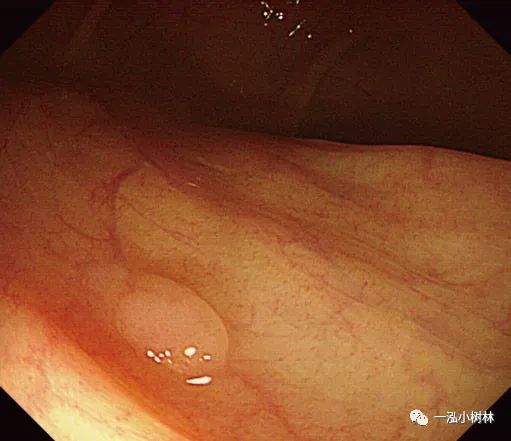

图1c 小息肉切除瘢痕,5年后腺瘤复发

图1d NBI观察